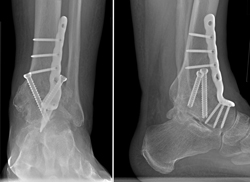

These x-rays show an ankle fusion from the front and the side. The number and placement of screws and the use of a plate are dependent upon the surgeon's technique.